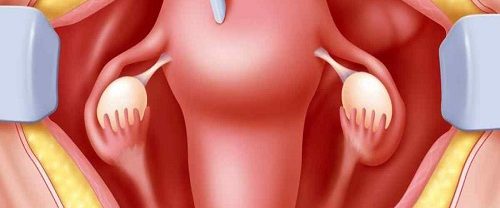

Over Kisti Patlojileri Over Kisti Patlojileri, bir kadının yumurtalıklarında oluşan sıvı dolu keseciklerdir. Bu kistler genellikle hormonal değişiklikler veya yumurtalıkların normal fonksiyonlarında meydana gelen bozukluklar sonucunda gelişebilir. Çoğu over kisti benigndir (iyi huylu) ve kendiliğinden kaybolabilir. Ancak, bazı durumlarda kistler büyüyebilir, ağrıya neden olabilir veya komplikasyonlara yol açabilir, bu durumda cerrahi müdahale gerekebilir. Over Kisti…

Myomektomi Nedir? Myomektomi, rahimdeki miyomların cerrahi olarak çıkarılması işlemidir. Miyomlar, rahim duvarının kas dokusundan oluşan benign (iyi huylu) tümörlerdir. Bu tür tümörler genellikle kadınların üreme çağında görülür ve genellikle hormonlarla ilişkilidir. Miyomlar, adet döneminde artan kanama, ağrı ve pelvik baskı gibi semptomlara neden olabilir. Büyük veya belirli bir konumda bulunan miyomlar ayrıca hamilelik sırasında komplikasyonlara…

Histerektomi Rahim Alınması Nedir? Histerektomi Rahim Alınması, bir kadının rahminin tamamen veya kısmen cerrahi olarak çıkarılması işlemidir. Bu prosedür, çeşitli sağlık sorunlarına çözüm olarak uygulanabilir. Rahmin alınması, genellikle aşağıdaki durumlar için gereklidir: Rahim Kanseri veya Prekanseröz Durumlar: Rahim kanseri teşhisi konulmuş veya rahim hücrelerinde kanser öncüsü değişiklikler tespit edilmişse, histerektomi tedavi seçeneklerinden biri olabilir. Myomlar…

Endometriozis Nedir? Endometriozis, kadınların üreme sistemini etkileyen bir sağlık sorunudur. Normalde rahim iç tabakasını oluşturan dokunun, rahim dışında (genellikle karın boşluğunda) bulunması durumunu ifade eder. Bu durumda, adet döneminde rahim iç tabakasına benzer şekilde doku büyür, kalınlaşır, kanar ve sonunda dökülür. Ancak, bu doku vücut dışında olduğu için dökülen kan vücuttan atılamaz ve çevredeki dokulara…